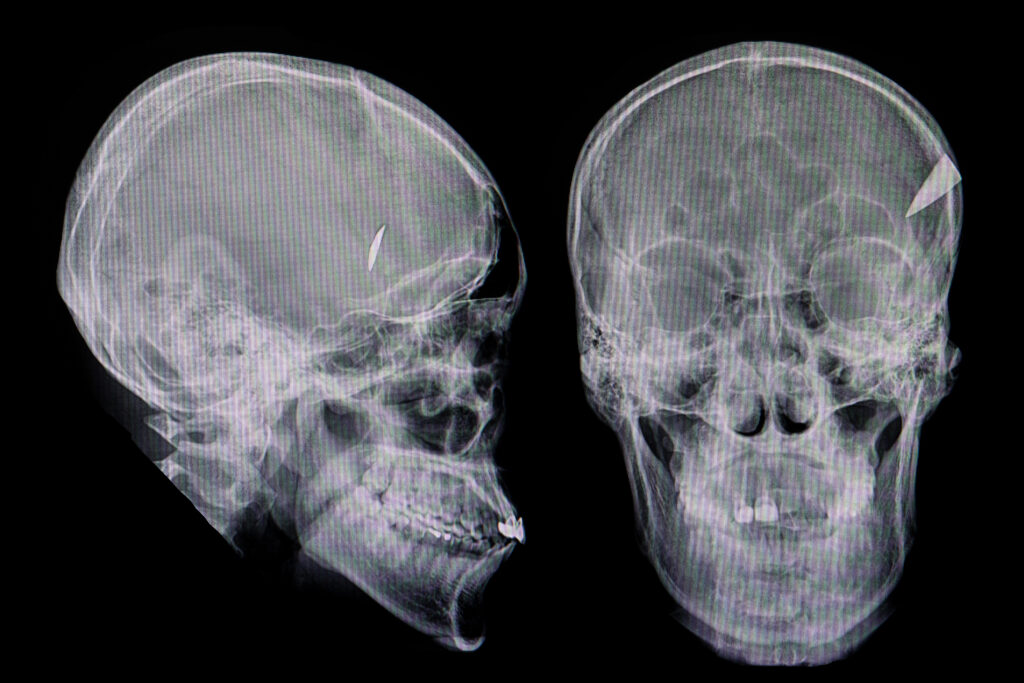

TOMOGRAFÍA CBCT: DIAGNÓSTICO 3D AVANZADO

La tomografía Cone Beam (CBCT) ofrece una visión tridimensional detallada de dientes, huesos y articulaciones, con mínima radiación. En IDD contamos con protocolos modernos para garantizar diagnósticos seguros y confiables.

Diagnóstico tridimensional preciso.

Planeación exacta de implantes y cirugías.

Evaluación de patologías en maxilares y senos paranasales.

Tecnología de vanguardia para ortodoncia y ATM.